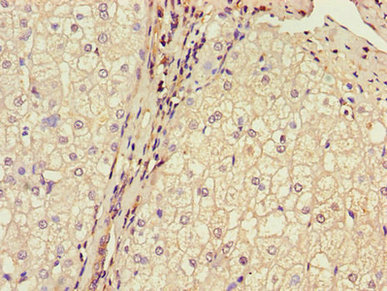

Immunohistochemistry of paraffin-embedded human liver cancer using CSB-PA002816LA01HU at dilution of 1:100